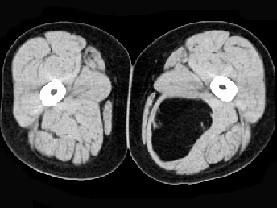

问题 女性,52岁,感左小腿肿胀两年余,活动后稍加重,不痛不热,请结合所提供的图像,选择最佳答案 ( )

选项 A、大腿囊肿 B、大腿脂肪瘤 C、大腿畸胎瘤 D、大腿平滑肌瘤 E、大腿错构瘤

答案 B